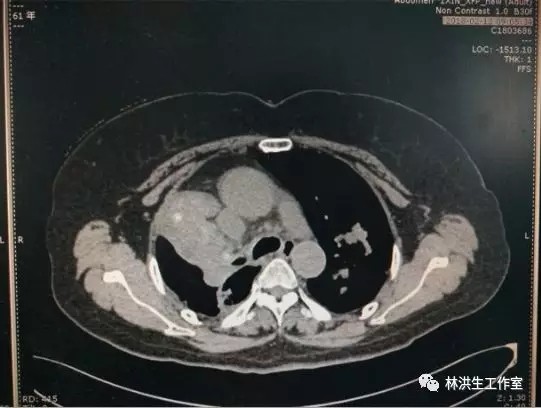

【诊断】右肺上叶癌 双肺多发转移 脑转移 IV期

【现病史】患者2013年4月诊断右肺低分化腺癌(7.4*5.6cm),双肺多发转移,基因检测:EGFR(-)。行培美曲塞+奈达铂方案4次化疗及氩氦刀治疗后肿物缩小(5.5*4.8cm),疗后评价:缩小SD。中西医结合至今,病灶进展缓慢,体力评分PS100分。

2013-8中药治疗前:右肺肿物6.5*5.2cm